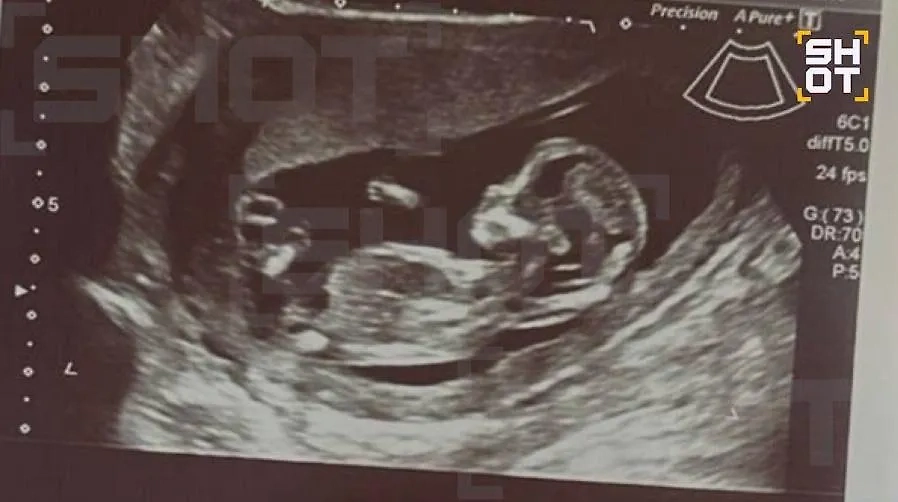

Врач акушер-гинеколог, которого цитирует SHOT, отметил, что хирургические вмешательства и приём некоторых препаратов на столь ранних сроках могут быть опасны для плода, вплоть до развития тяжёлых нарушений. Однако, несмотря на все опасения, пока беременность Дианы развивается нормально. Первое обследование показало, что никаких отклонений у ребёнка не выявлено.